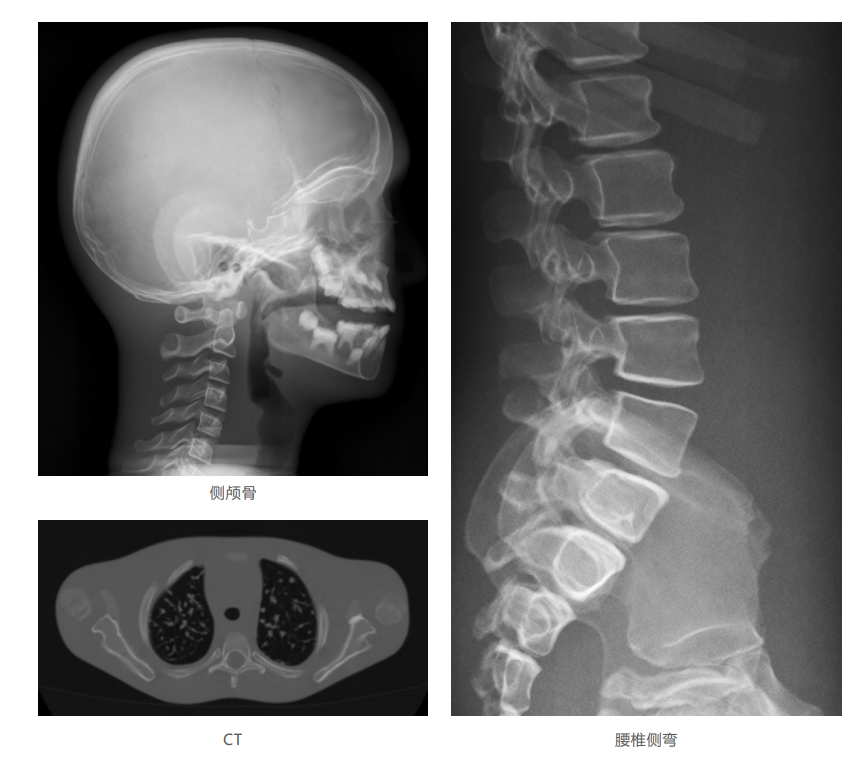

模體掃描成像圖:

仿真兒童培訓(xùn)模體旨在幫助教學(xué)和提高患者對體位、準(zhǔn)直和解剖學(xué)的理解,其廣泛的特點(diǎn)有助于安全、高質(zhì)量的兒科影像學(xué)的有效指導(dǎo)。 模體的大小和結(jié)構(gòu)都代表了典型的5歲兒童,使其便攜和易于定位。包括頭、胳膊和腿在內(nèi)的整個身體高110厘米,重20公斤。該系列包括六個部分的模體可單獨(dú)或作為一個完整的集合。 右肢有伸直或彎曲兩種配置。左臂和左腿可選伴有或不伴有內(nèi)嵌骨折。 骨折版本包含最常見的兒科骨折類型,包括脛骨扣帶骨折和腓骨普通骨折;第一跖骨骨折;橈骨切開復(fù)位骨折,第二中間趾骨常見骨折。 組件由適當(dāng)?shù)木郯滨ズ铜h(huán)氧材料制成,模擬人體組織的 X射線衰減特性,用于診斷和治療能量范圍(50 keV - 25 MeV) 。 材料經(jīng)久耐用,耐沖擊,適合連續(xù)搬運(yùn)。透明的軟組織有助于解剖標(biāo)志的視覺指示。